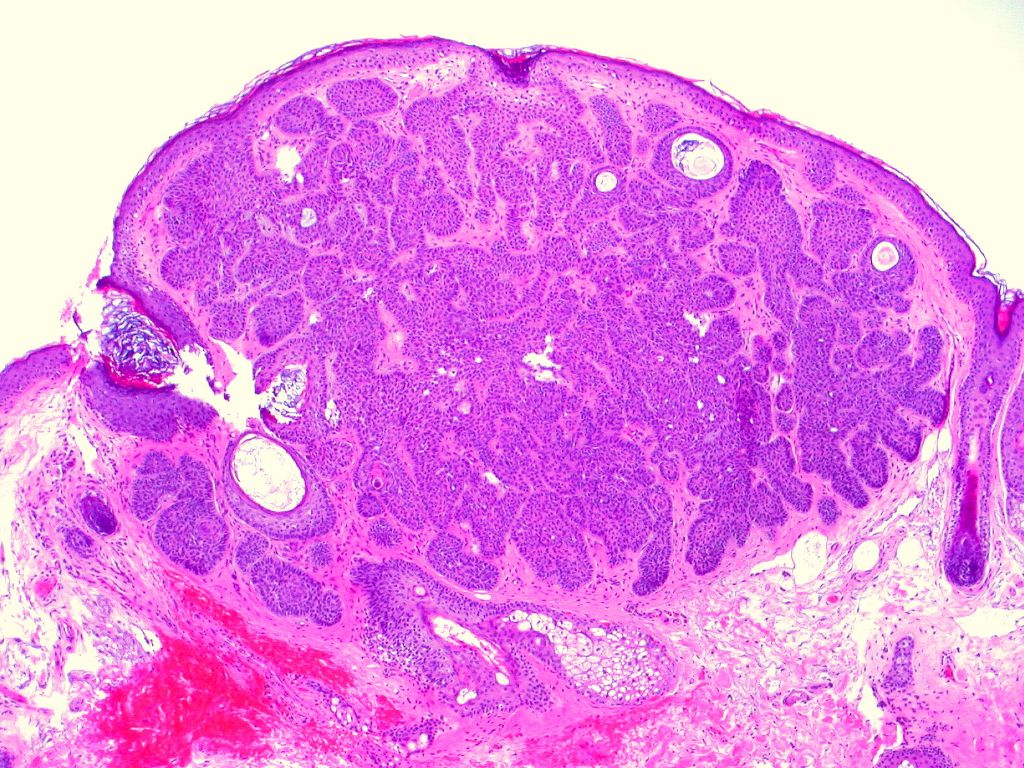

Desmoplastisch trichoepithelioma

Variant van trichoepithelioom, solitair en niet-familiair. Asymptomatische solitaire

harde annulaire laesies met een opgeworpen rand en een ingedeukt centrum. Het

desmoplastisch trichoepithelioom

kenmerkt zich door langzame groei, soms door locaal invasieve proliferatie van

weefsel waarin overwegend haarfollikel elementen voorkomen. Histopathologisch

zijn er drie kenmerken: 1. aanwezigheid van veel met hoorn gevulde cysten; 2.

aanwezigheid van ketens van kleine, basofiele tumorcellen; 3. een dicht fibreus

stroma dat de eerste twee structuren omringt. De opvallende uitgesproken palissadering

zoals bij het basaalcelcarcinoom is afwezig. Er is wel overeenkomst met het

sclerosend basaalcelcarcinoom, dat echter veel minder cysten heeft.

desmoplastisch

trichoepithelioom |